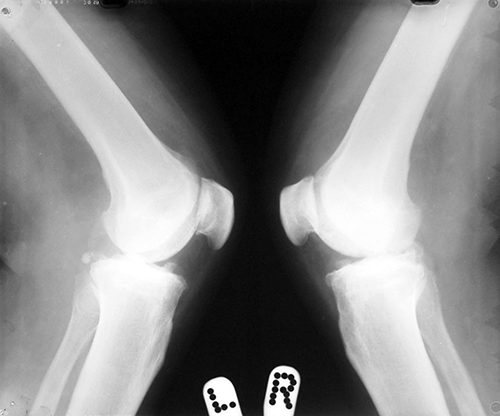

Case:5 RollTendon Arthroplasty

Arthroscopy Surgeon in Ahmedabad|Limb Reconstruction Doctor

Pre-Op

Arthroscopy Surgeon in Ahmedabad|Spine Treatment In Jaipur

Post-Op